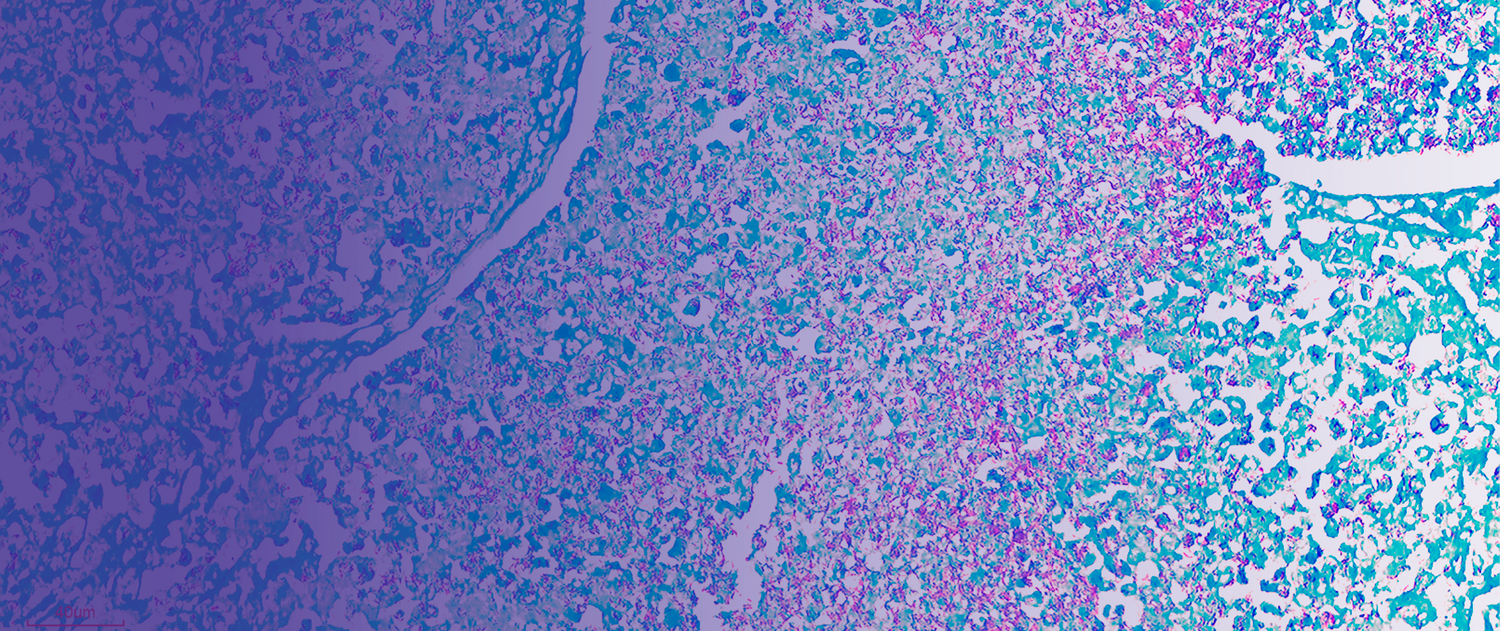

GALERÍA DE IMÁGENES